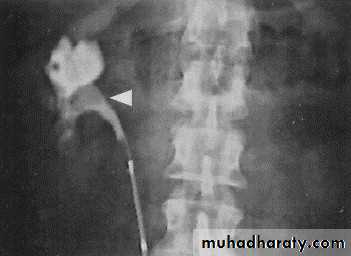

Acutely obstructed kidney shows a dense nephrogram (dense opacification of the renal parenchyma).excretion of contrast (opacification of the collecting system which may take many hours), then the level and degree of obstruction can be determined as dilated pelvi-caliceal system and ureter are followed down to the point of obstruction (point of hold up).

Pyeloxinus reflux may result from rupture of a fornix precipitated by contrast-induced diuresis superimposed on the increased hydrostatic pressure of an obstructed pelvicaliceal system. Urine and contrast extravasate into the renal sinus and perirenal space .

Radiolucent stones appear as filling defect on IVU.